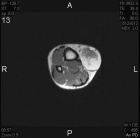

49 year old male with slow growing cystic mass over distal aspect right leg.

Zoom image: Radiological image Radiological image.